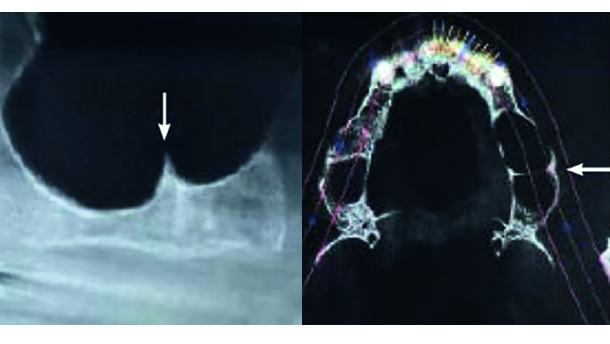

Relationship between preoperative Cone Beam Computed Tomography and intraoperative findings in sinus augmentation (Int J Oral Maxillofac Implants. 2015 Nov-Dec;30(6):1244-8.) (Figs. 1a & b).

Maxillary posterior areas present problems for placing implants due to diminished bone height, low bone density and anatomic restrictions of the maxillary sinuses that lie above the alveolar ridges. When the residual ridge is 5 mm or less, a sinus augmentation procedure is commonly used to augment the amount of available bone for implant placement. The maxillary sinus must be completely evaluated for anatomic and/or pathologic findings prior to any surgical intervention. Failure to do so could lead to post-operative surgical morbidity, such as infection. Cone Beam Computed Tomography (CBCT) is becoming the gold standard for pre-operative Sinus examination due to its low distortion and comparatively low radiation compared to conventional CT. Although the radiation dosage is slightly higher than a panoramic X-ray, you have the added advantage of viewing the sinuses in 3 dimension. The most common complication during sinus surgery is membrane perforation resulting during the opening of the bony window or during elevation of the membrane. This study compared pre operative CBCT to intraoperative findings to see if there was greater risk of perforation during elevation in the presence of bony septum, thin Schneiderian membranes and reduced residual ridge height.

PreoperativeScans from an ICAT Next Gen CBCT (Imaging Sciences International, Hatfield, PA) were taken and evaluated for several criteria. Bony septum were evaluated using axial slices, Membrane thickness was measured using the coronal slices and the residual ridges evaluated using sagittal slices. Also, intraoperatively, it was noted whether perforation occurred and how long the surgery took. The results were that membrane perforation occurred in 24.5 % of the cases. In cases with the presence of septum, membrane perforation occurred 57.1 % of the time. Otherstudies have suggested that the presence of septum is the reason for membrane thinness. While the mean membrane thickness in the study was 3.96 ± 2.01 mm, there was no significant correlation between membrane thickness and occurrence of perforation. Also, the residual ridge bone height had no significant correlation with the occurrence of membrane perforation. In summary, CBCT is an important tool in the preoperative patient evaluation so that sinus septum can be identified to reduce the risk of membrane perforation.